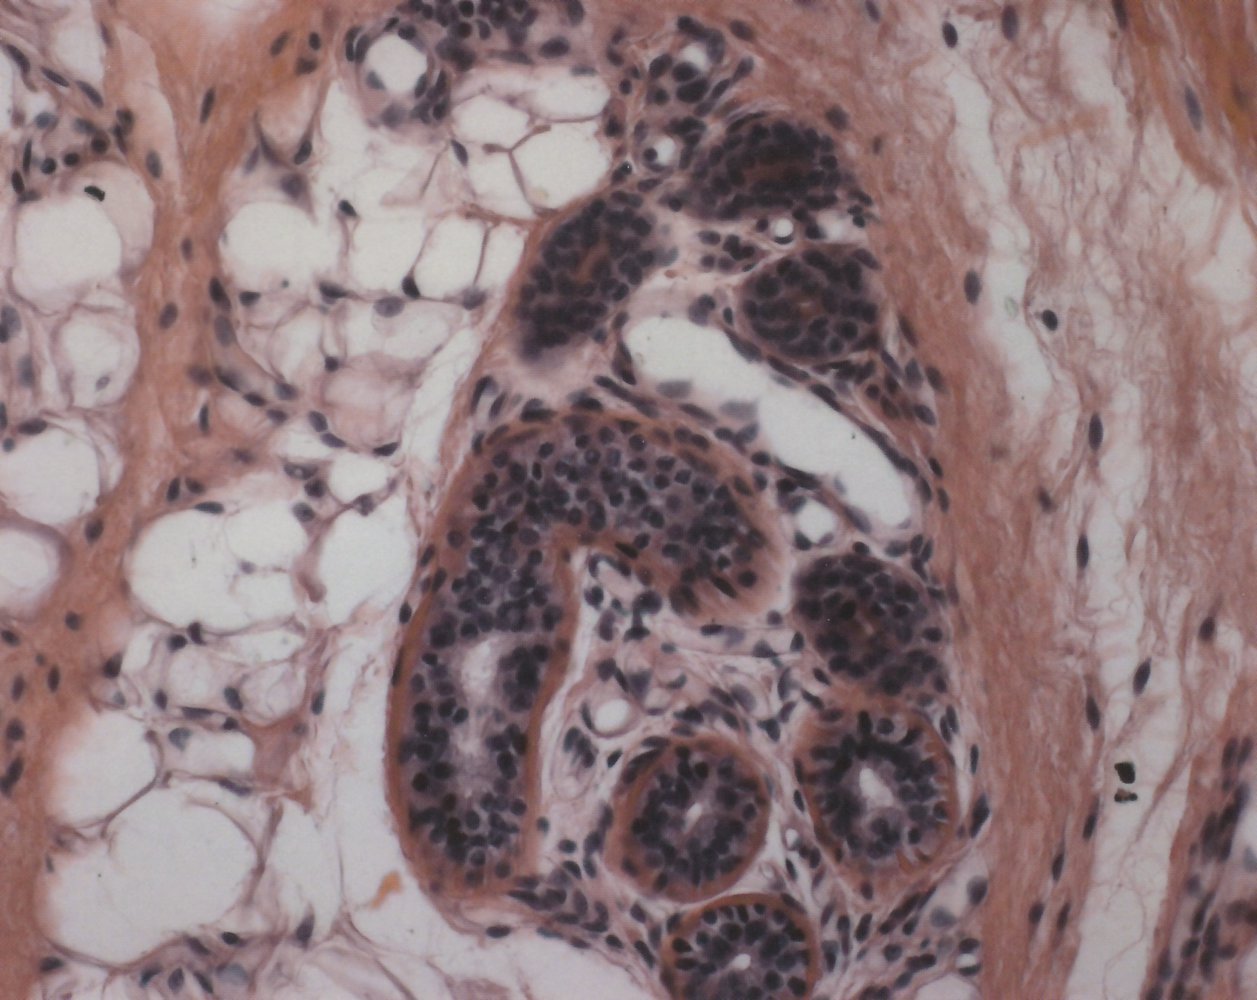

• Terminal hair follicle

• Extends into subcutaneous fat

• Found on the scalp, eyebrows, and eyelashes

Glands

Sebaceous glands Sweat glands

Eccrine sweat glands Apocrine sweat glands

Description

• Exocrine (holocrine) branched glands

• Composed of a secretory unit called glomerulum or acrosyringium; surrounded by myoepithelial cells

• The combination of sebaceous gland, arrector pili muscle, and hair follicle is known as the pilosebaceous unit.

• Exocrine glands with a spiral duct (acrosyringium) and secretory ducts that open into sweat pores

• Exocrine glands with a secretory unit (glomerulum) and excretory ducts that open into hair follicles

Location and distribution

• Dermis

• Predominantly located on the face and scalp

• Absent on palms and soles

• Deep in the dermis and hypodermis

• Most areas of the body

• Absent in lips, ear canal, clitoris, labia minora, and glans penis

• Mostly axilla, perineum, areola of the nipple, and external ear